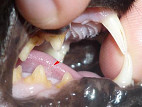

Кошка 12лет. Месяц назад начала драть лапой во рту, отвели к ветеринару. Врач указал на опухоль(качественная или злокачественная не определил), выписал антибиотики, цитостат, эвинтон. После курса антибиотиков, кошка перестала драть рот, появился аппетит, но вот опухоль не исчезла. А позже дали кошке антисекс, через день ее снова начала тревожить опухоль. Продолжаем прием цитостата. Посоветуйте какие препараты здесь уместны, какое лечение?? Фото прилагаю И опухоль ли это???

Центральная ветеринарная клиника ул.Проспект победы здесь сказали, что это опухоль, а на соколе вырвали зубки, обьяснив это пародантозом.

Это опухоль, хотя видно не очень хорошо. У кошек в этом месте часто развивается плоскоклеточный рак. Поддается он только лучевой терапии.